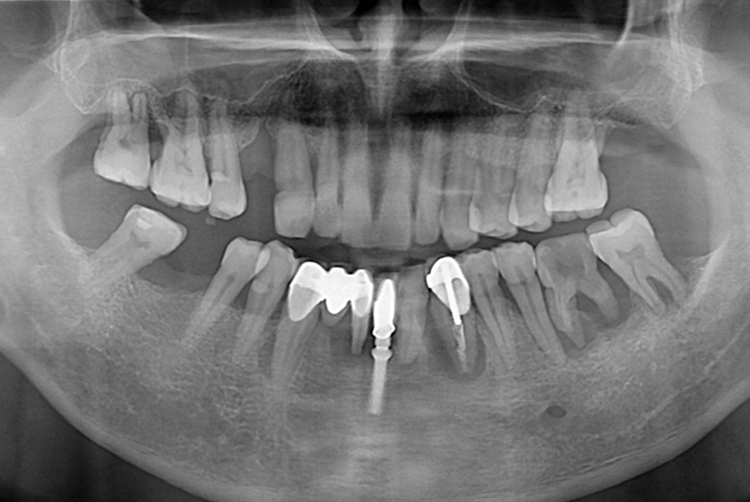

[임플란트] 임플란트

치료후 : 2019-10-31

세종치과는 많은 환자와 다양한 케이스를 바탕으로 항상 편안한 임플란트 수술을 제공하고자 노력하고,

오래동안 튼튼히 쓸 수 있는 임플란트 수술을 가장 큰 목표로 삼고 있습니다